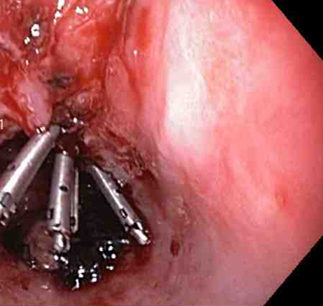

[Figure caption and citation for the preceding image starts]: Adrenalina é injetada localmente ao redor do local da laceração de Mallory-WeissDo acervo de Juan Carlos Munoz, MD, University of Florida [Citation ends].

Os clipes do tipo "through-the-scope" (TTSC), isolados ou em combinação com injeção de adrenalina, podem controlar efetivamente lesões com sangramento ativo; os clipes são tão eficazes e seguros quanto outros métodos.[74][75][76] De acordo com a experiência dos autores, esta é a técnica de escolha em pacientes com laceração ou ruptura com sangramento ativo. A aplicação de TTSCs e ligadura com nó de forca no esôfago também foi descrita como um método para fechamento de grandes lacerações de Mallory-Weiss.[77][Figure caption and citation for the preceding image starts]: Um clipe do tipo "through-the-scope" instalado no centro da lesão (sem infusão prévia de adrenalina, neste caso)Do acervo de Juan Carlos Munoz, MD, University of Florida [Citation ends].